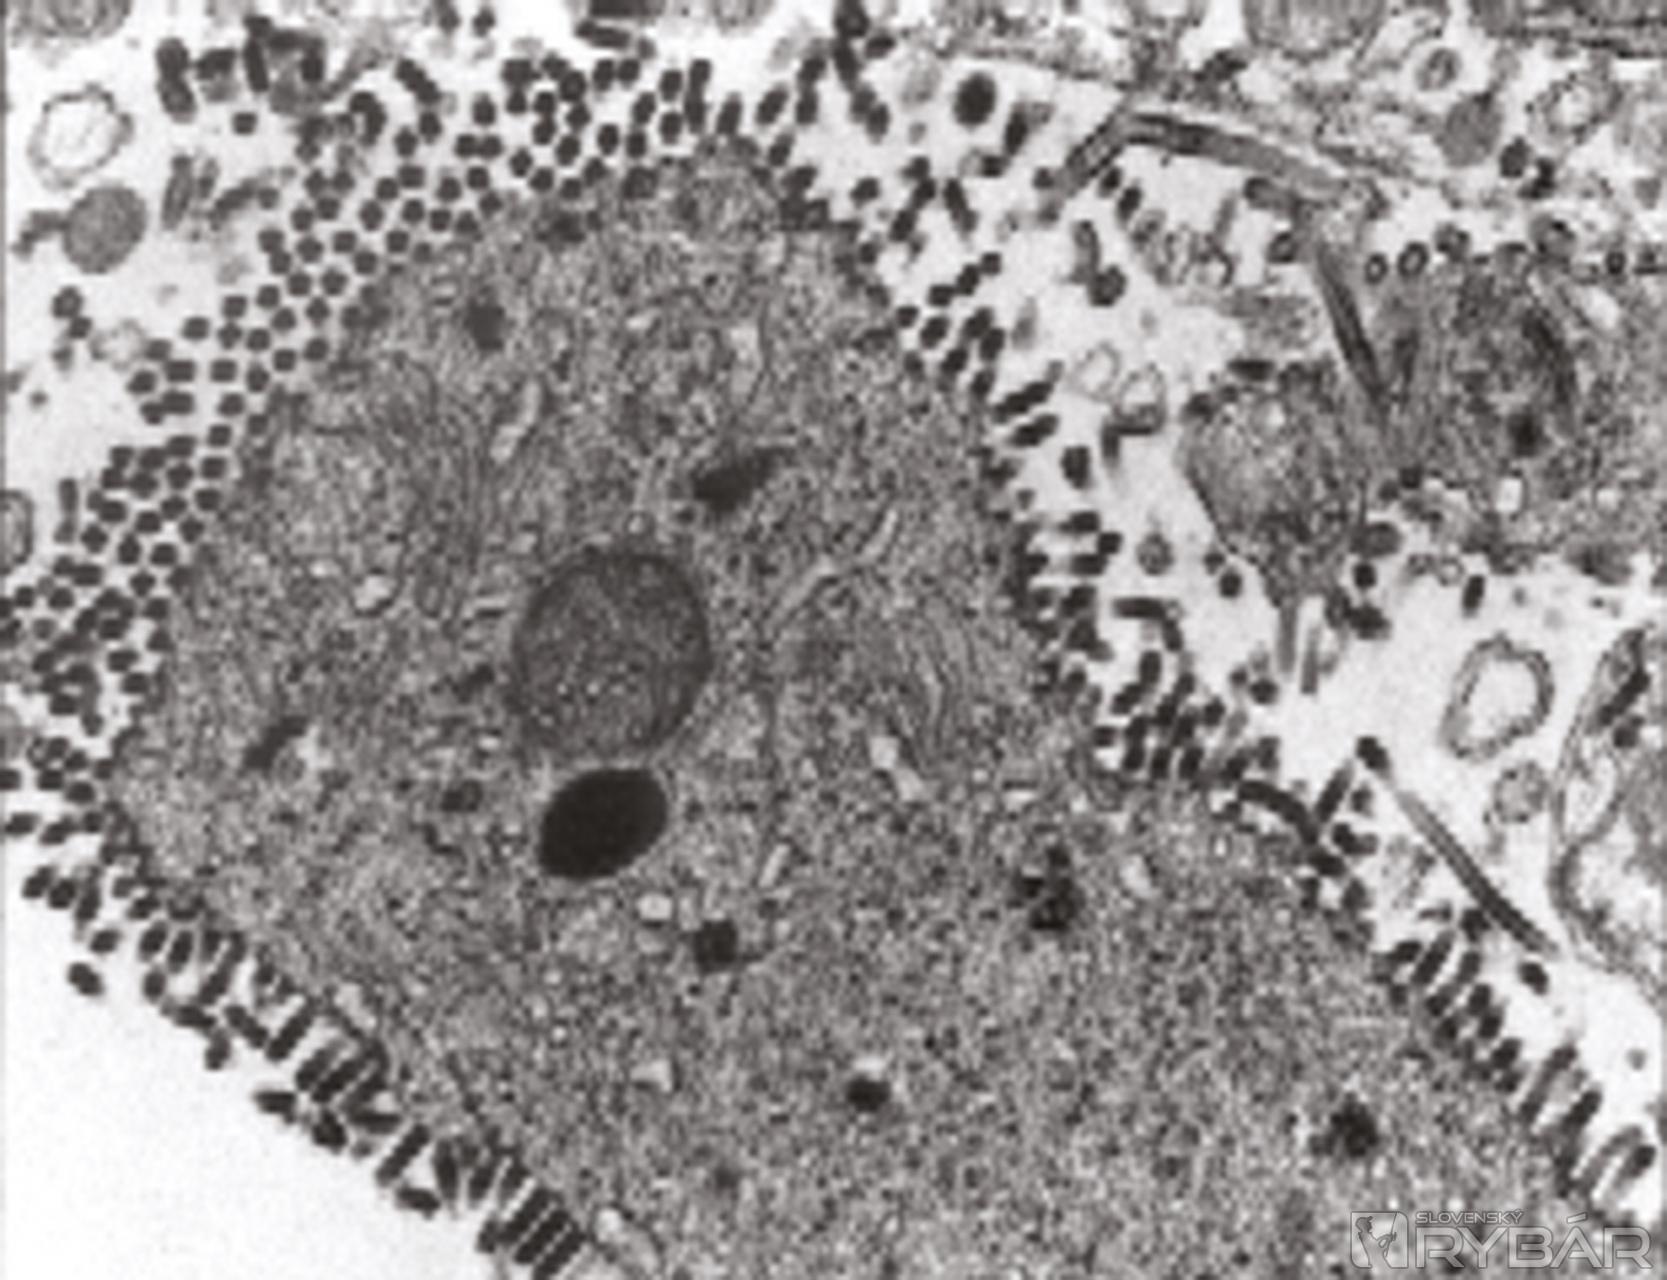

Pôvodca VHS: vírus zo skupiny rabdovírusov dosahujúci veľkosť 180 – 240x60 – 75 nm.

Príznaky ochorenia sa prejavujú 7 – 15 dní po nákaze. Jej štádium býva akútne, kedy straty dosahujú 50 a viac percent z obsádky, a chronické. Vírus napáda nadobličkový systém (pravé nadobličky ryby nemajú) a krvným riečiskom sa dostáva aj do iných orgánov a celého tela. Vírus poškodzuje krvné kapiláry, preto dochádza k drobným krvným výronom. Postihnuté orgány degenerujú, nastupuje celková anémia a obmedzenie exkrečnej činnosti.

Chorobné zmeny: ryby sú nápadne tmavé (zo začiatku na chrbte, neskôr aj na bokoch), častý je exoftalmus (vypúlenie očí), žiabre sú výrazne bledé, nedokrvené, v koži pri báze plutiev sa objavujú menšie krvácaniny (hemoragie), ktoré už pozorujeme i vo svalovine a vnútorných orgánoch, nadobličkový systém (nesprávne obličky) je zdurený až granulovaný, výrazne hrboľatý, tmavočervený až šedivastý, v telesnej dutine sa hromadí tekutina, črevo je stenčené.